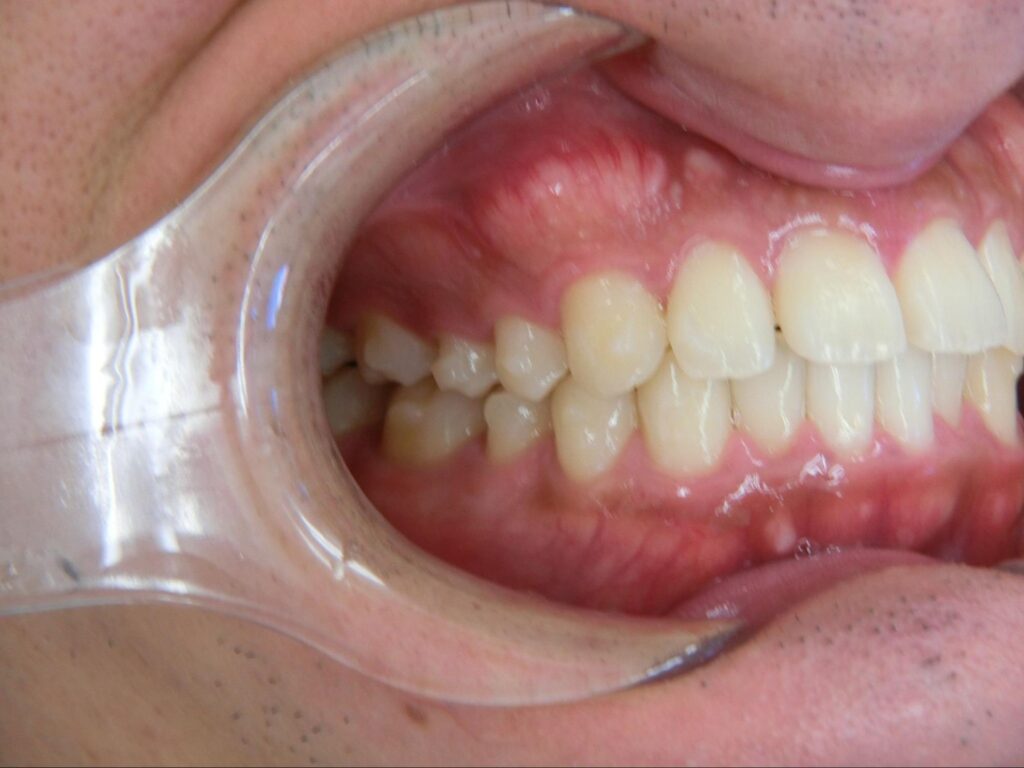

下記のケースでは、奥歯の噛み合わせが悪くなかったことから、患者様の希望もあり、部分矯正で対応いたしました。

上顎の前歯が大きく突出しています

明らかに前歯の突出感が改善し、患者様はこの時点でとても喜ばれていました

矯正治療終了時 部分矯正ということもあり、短期間で矯正治療を終了することができました